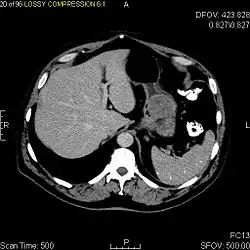

Tomografia komputerowa (TK) pełni rolę w rozpoznaniu choroby, ocenie jej zaawansowania oraz planowaniu postępowania chirurgicznego[47][2][5][44]. W tomografii komputerowej GIST jest obrazowany jako dobrze odgraniczona zmiana poza światłem przewodu pokarmowego[2]. Gęstość zmian jest różna, zmiana może ulegać niejednolitemu wzmocnieniu kontrastowemu[5], co jest szczególnie zaznaczone przy większych guzach z obecną martwicą i obszarami krwotocznymi[2]. Typowo obraz jednorodnego wzmocnienia kontrastowego przemawia za łagodnym charakterem zmiany[10]. Tomografia komputerowa jest przydatna w rozpoznawaniu przerzutów odległych, szczególnie do wątroby[2]. Rezonans magnetyczny (RM) jest przydatny w ocenie zmian zlokalizowanych w miednicy oraz oceny rozsiewu do otrzewnej[2].